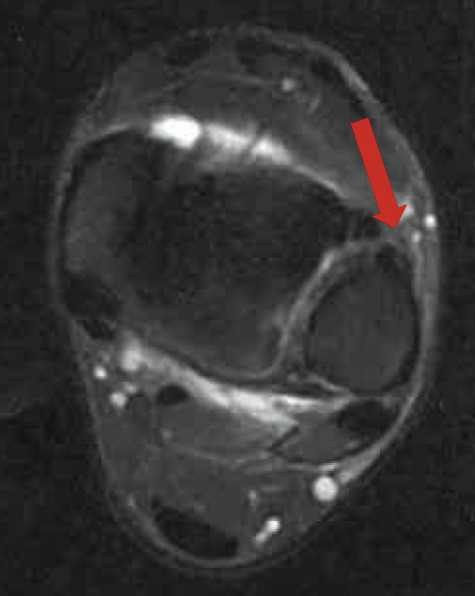

Une IRM confirme l’entorse grave dite « de la syndesmose », avec rupture complète du ligament tibiofibulaire antéro-inférieur (LTFAI) et de la membrane interosseuse (fig. 2 et 3 ), mais le ligament tibiofibulaire postéro-inférieur (LTFPI) est intact. L’absence de diastasis tibiofibulaire au bilan radiologique complémentaire classe la lésion en stade 2 (fig. 4).

Une IRM confirme l’entorse grave dite « de la syndesmose », avec rupture complète du ligament tibiofibulaire antéro-inférieur (LTFAI) et de la membrane interosseuse (